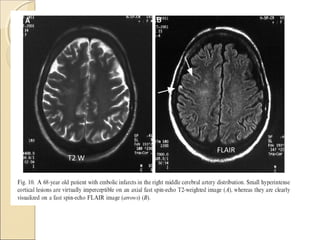

More sensitive for detection of acute

infarct…differentiate it from cystic

encephalomalacia

Useful in SAH …removes CSF signal